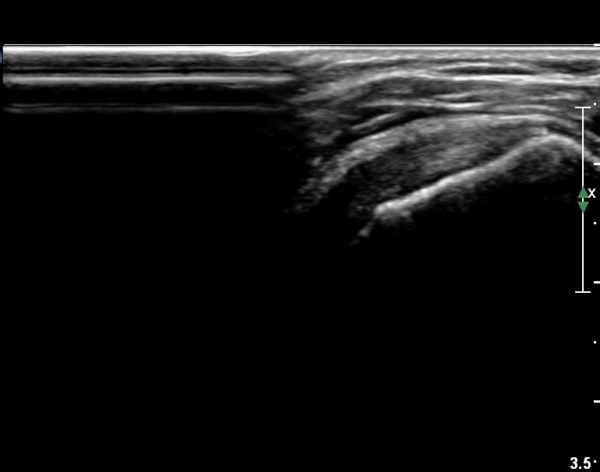

ÃÊÀ½ÆÄ ¼Ò°ß :  ±Ø»ó°Ç Á¾´Ü¸é°Ë»ç¿Í Ⱦ´Ü¸é°Ë»ç»ó ƯÀÌ ¼Ò°ß º¸ÀÌÁö ¾ÊÀ½(»çÁø 1, 2).

°ß°©ÇÏ±Ù°Ç ÇϺΠÁ¾´Ü¸é°Ë»ç¿¡¼­ °ß°©Çϱٰdz»  ÀÛÀº ¼®È¸È­ µ¢¾î¸®°¡ °üÂûµÈ´Ù(»çÁø 3, 4).